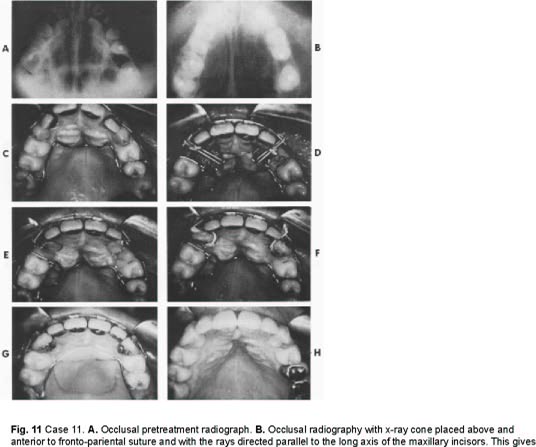

Case 8 (Figs. 10, 11, and 12) Miss D. L. Age 26

CLASS D 1 + 3 (Major orthodontics, prosthetic restoration; orthodontic retention, fixed splinting). Treatment time-- 33 months. Reason for treatment-- Patient concerned with the appearance of her teeth and the health of her mouth. She came from a small town where no orthodontic treatment was available. She now has an important position and wishes to do whatever is possible to improve herself. Orthodontic treatment--

• 1. Upper right 4, 5, 6 and left 4, 5 expanded.

• 2. Upper incisors aligned. Laterals moved labially.

• 3. Lower 3, 4, 5s contracted.

• 4. Lower incisors retracted and all six anteriors aligned.

• 5. Upper and lower left bicuspids moved slightly mesially.

• 6. Upper left 7 moved distally to upright.

• 7. Upper Cs extracted, 3s surgically exposed, pinned, and moved orthodontically into alignment.

• 8. Upper right 8 and retained roots in lower edentulous areas extracted. Appliances--

• Maxillary-- fixed bands. Mandibular-- first removable, then fixed bands.

Fig. 10 Case 8. A. Initial appliances (maxillary fixed bonds and mandibular low labial removable appliance with posterior bite plane). B. After correction of anterior and posterior crossbites. Note spring soldered to end tube of maxillary twin arch and attached to pin cemented to upper right cuspid to draw it incisally. C After placement of band on upper right cuspid. Note elastic thread ligature to rotate it and move it incisally. D. Prior to band removal.

Fig. 11 Case 11. A. Occlusal pretreatment radiograph. B. Occlusal radiography with x-ray cone placed above and anterior to fronto-pariental suture and with the rays directed parallel to the long axis of the maxillary incisors. This gives o true cross-sectional appearance and more accurately locates impacted canines. C. Initial appliances. D. Following exposure and pinning of upper cuspids. Note elastic thread ligature from pins to twin wire. E. Cuspids approaching alignment. F. Bands cemented to cuspids. Elastic thread ligature used for rotation. G. Cuspid alignment almost completed. Note acrylic button added to Mershon lingual appliance for additional anchorage. H. Completed maxillary arch.

Fig. 12 Case 8. A,B,C. Before treatment. D,E,F. After orthodontic treatment and prosthetic restoration.